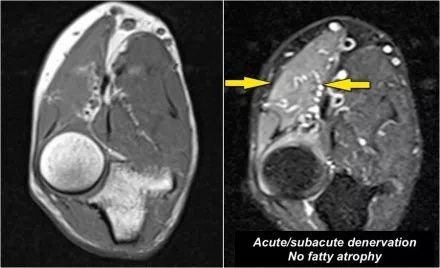

失神经支配:当神经炎或神经受压时,神经病理可表现为神经增厚。神经病理学的次要征象是肌肉水肿和/或萎缩的去神经支配。在这种情况下,T1上有高信号的慢性萎缩,这是不可逆转的。在早期或亚急性去神经支配中,突出的征兆是在T2W图像上具有高信号的水肿并且是可逆的。

下面是一名患有马凡氏综合征的48岁男性,右手无力突然发作。这是亚急性去神经支配的一个很好的例子。关于T1W图像的注意事项,没有萎缩。只有T2W图像上的水肿。这是由于近端桡神经病变所致。